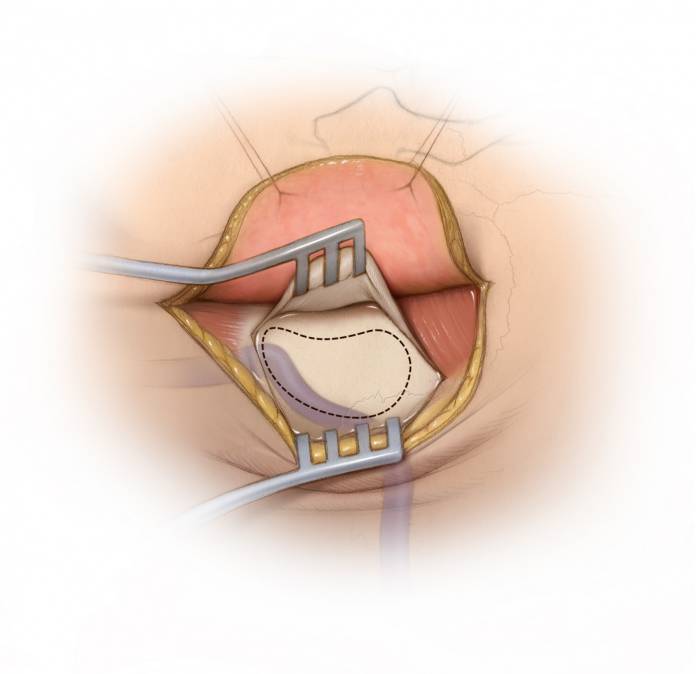

图12. 切断或撕脱前庭和/或蜗神经后,包膜外翻转肿瘤便可将其与IAC内的面神经沿外-内方向剥离开,此时使用电刺激有助于界定面神经的上下缘。